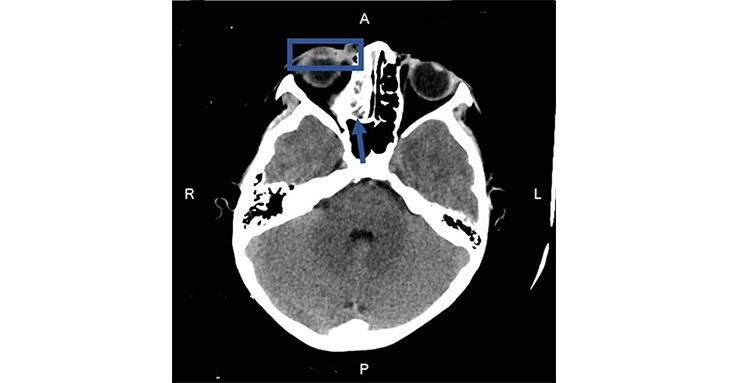

新竹臺大分院小兒部許瑋芸醫師診察後發現,男童右眼下眼瞼紅腫並壓痛,範圍超過下眼瞼。進一步抽血檢查顯示白血球數值及發炎指數顯著上升。醫療團隊隨即進行電腦斷層檢查並安排住院,經評估與檢查確診為「隔膜前(眼眶周圍)蜂窩性組織炎」。男童接受靜脈抗生素治療後,病況逐漸改善,後續改以口服抗生素治療,順利出院返家休養,並於門診追蹤,目前已完全康復。

CT影像顯示藍框處為右眼眼瞼發炎腫脹;箭頭處則是右側鼻竇炎。許瑋芸醫師表示,鼻竇炎惡化可能導致眼周感染,家長應留意孩子病況變化,避免延誤治療。(圖片提供/新竹臺大分院)